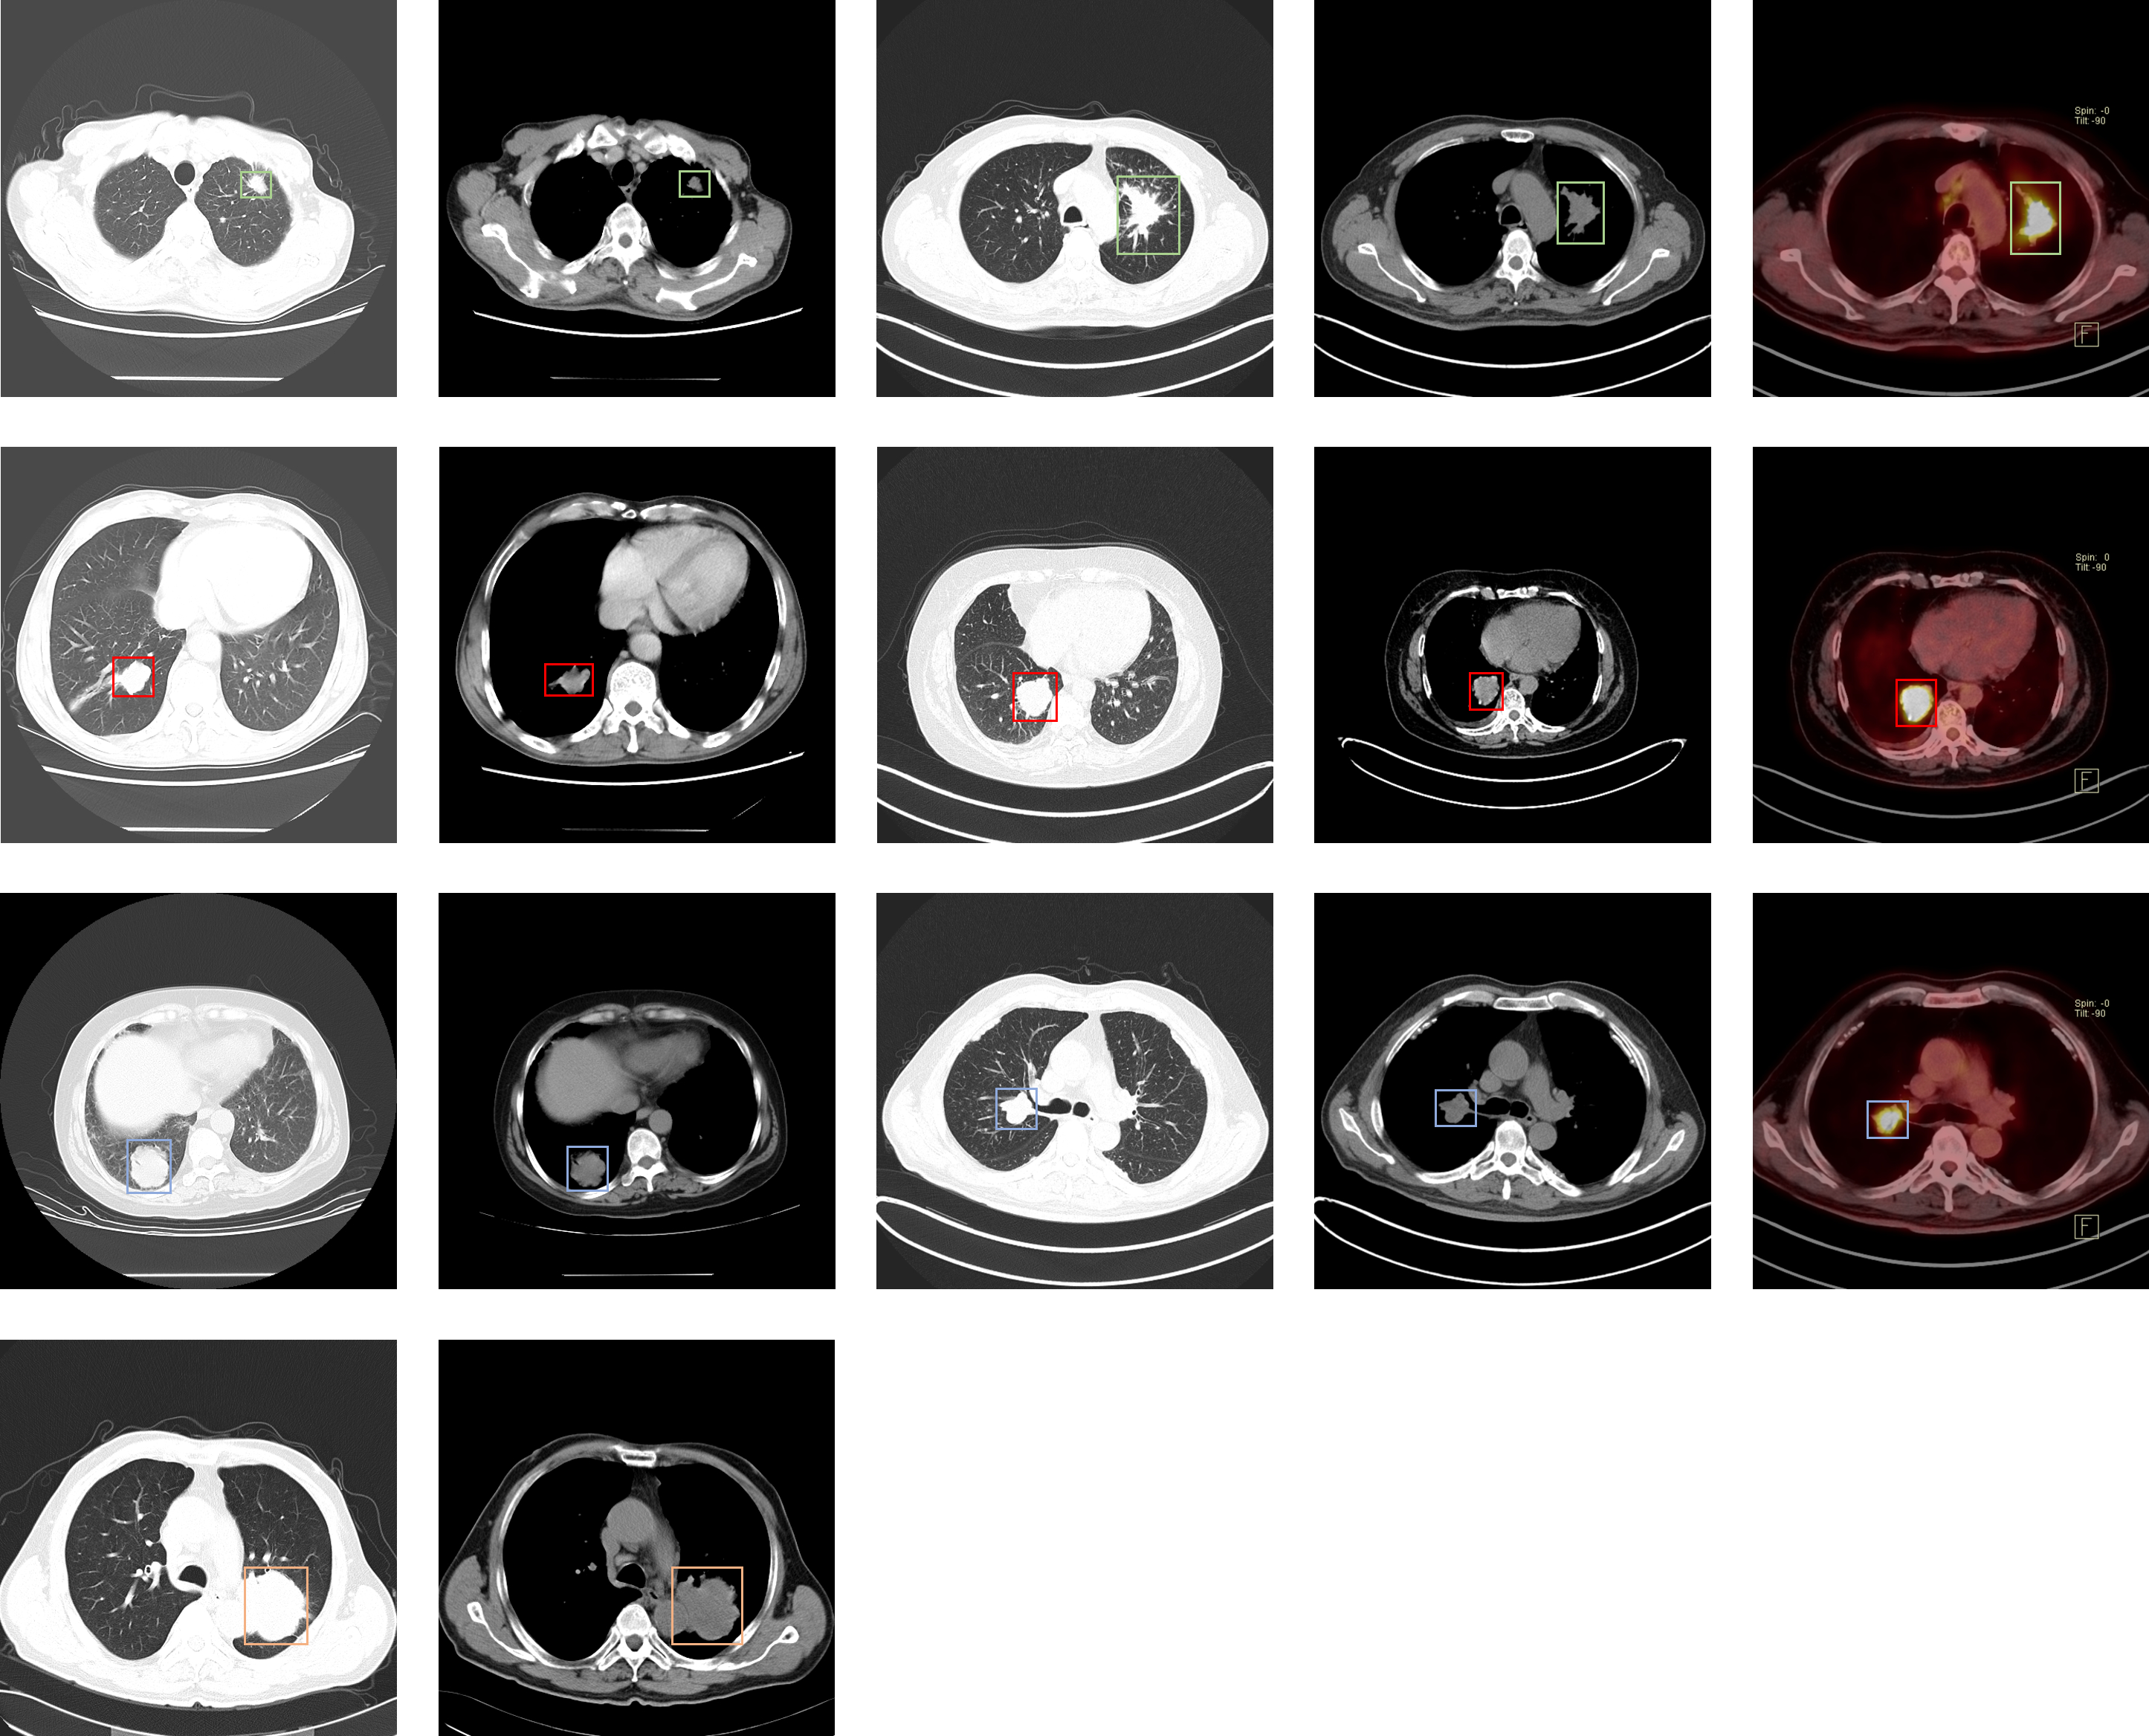

### Lung-PET-CT-Dx

| [Lung-PET-CT-Dx](https://wiki.cancerimagingarchive.net/pages/viewpage.action?pageId=70224216) | 肺癌 | 目标检测 | CT | 363 | xml | dcm |